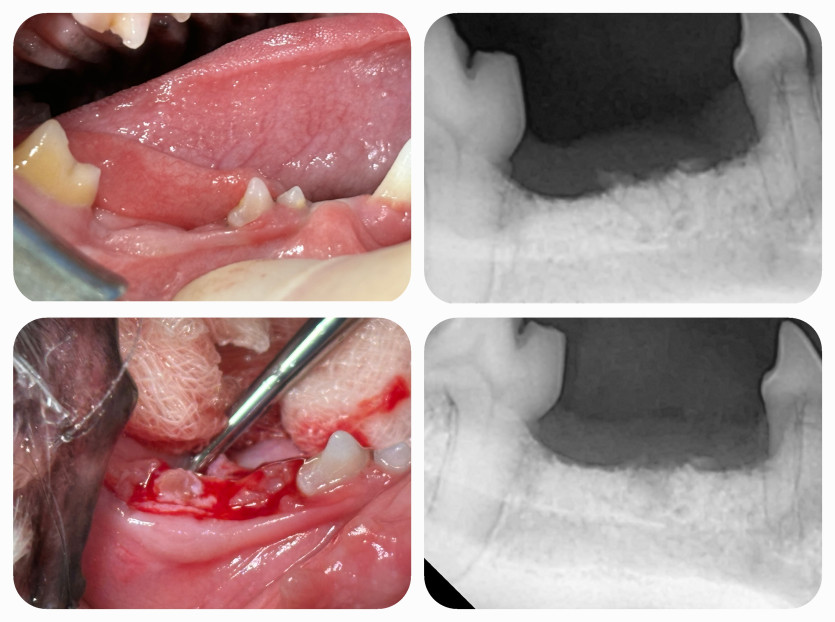

사막이의 잔존치근 치료후기

노령견이라 마취하고 안깰까봐 많이 걱정되었었는데

꼼꼼한 검사와 세밀한 체크 & 진료 덕분에 안심하고 진료 받았습니다.

수술 후에도 꼼꼼히 챙겨봐 주셔서 더 좋았어요.

안심하고 맡길 수 있는 병원인 것 같아요!!